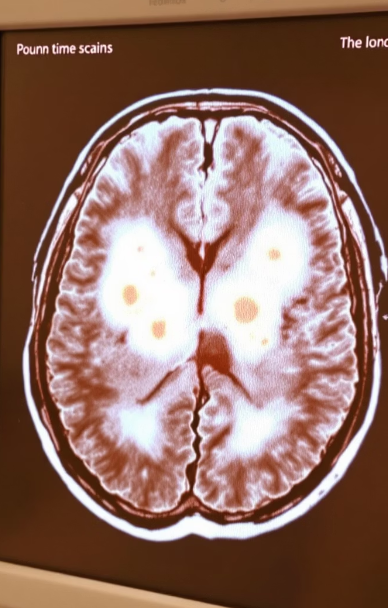

멜라스증후군(MELAS)은 생소하지만 결코 남의 이야기가 아닌, 유전성 미토콘드리아 질환입니다.

즉, 뇌와 근육에 손상을 일으키는 유전성 대사 질환으로, 주로 어린 시절이나 청소년기에 처음 나타납니다.

뇌졸중처럼 갑자기 말이 어눌해지거나, 의식 저하, 시야 장애 등이 나타날 수 있습니다.

멜라스증후군은 미토콘드리아 DNA의 돌연변이로 발생합니다.

특히 A3243G 돌연변이가 가장 흔하게 발견됩니다.